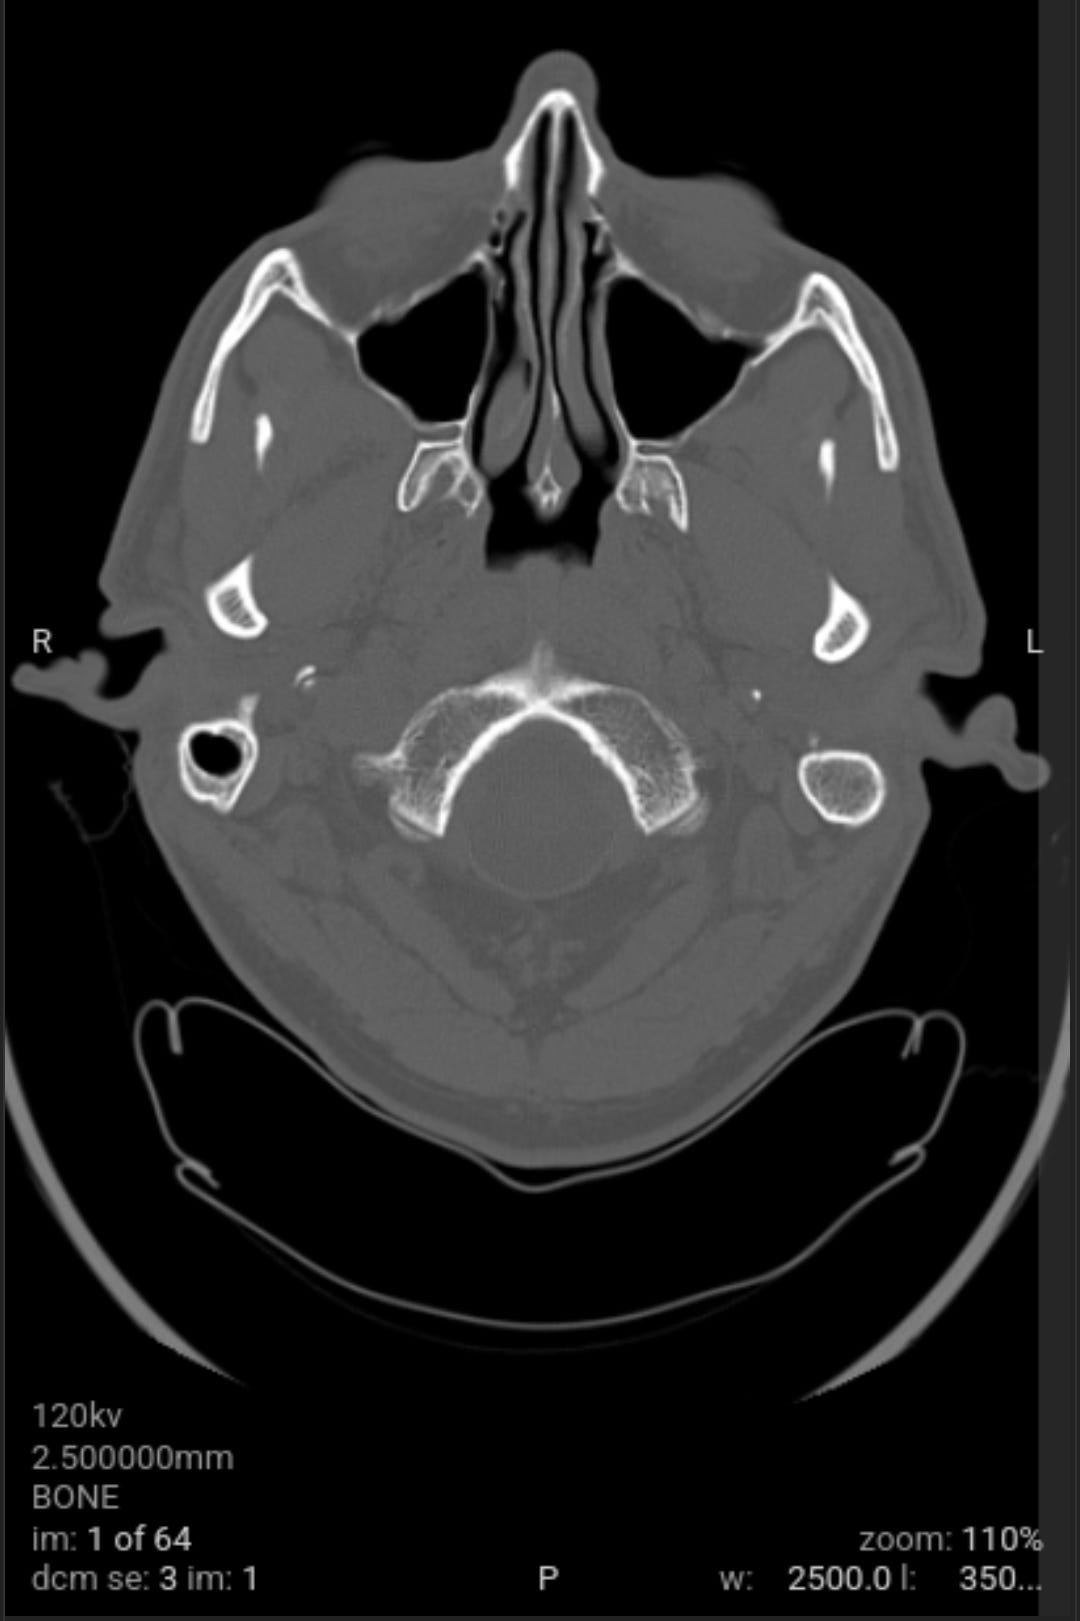

As a followup to eliminate all possible and probably causes of the weaponized audio-video-communications and pathogen nanotechnology. Got blood work and CAT scan done. Results came back good.

As a followup to eliminate all possible and probably causes of the weaponized audio-video-communications CNT and pathogen nanotechnology WPT, I got blood work and CAT scan done yesterday. All came back good with the exception of a low Red Blood Cell RBC count due to my cleansing diet on vegetables and plant based proteins that needs more iron in it with vitamin C, I already dose with vitamin B12 (preference is methylcobalamine). The medical staff could not determine what the unknown material removed from my body was from the salt baths or the material that moved around and itches at times on the left side of my head.

When I had the CAT scan test done, the free electron cascade reaction silenced the CNT local subnet. Anyone who has electronic harassment should know that this is the second time that I have confirmed a free electron cascade reaction destroys the circuitry that is programmed from your prior local environment LOTL CNT and global CNT as well as any mass transfer based CNT subnets. The first time I confirmed CAT scan quenched CNT by free electron cascade reaction was in late 2022 and now again in 2025 (although all of the work done from 2022 through today has significantly reduce the CNT junk, to nearly undetectable levels).

The void spaces on left side are what I suspect to be where the nanotechnology circuitry was removed by magnetic vortex skyrmion unit, chelators, salt water baths, no yeast diet and no added sugar diet. Note the scans do not show any nanotechnology based synthetic biology parasites. This is why the samples pulled from my body were classified as unknown by the western medical staff not trained in the nanotechnology and synthetic biology knowledge domain, a huge gap in Western medicine.